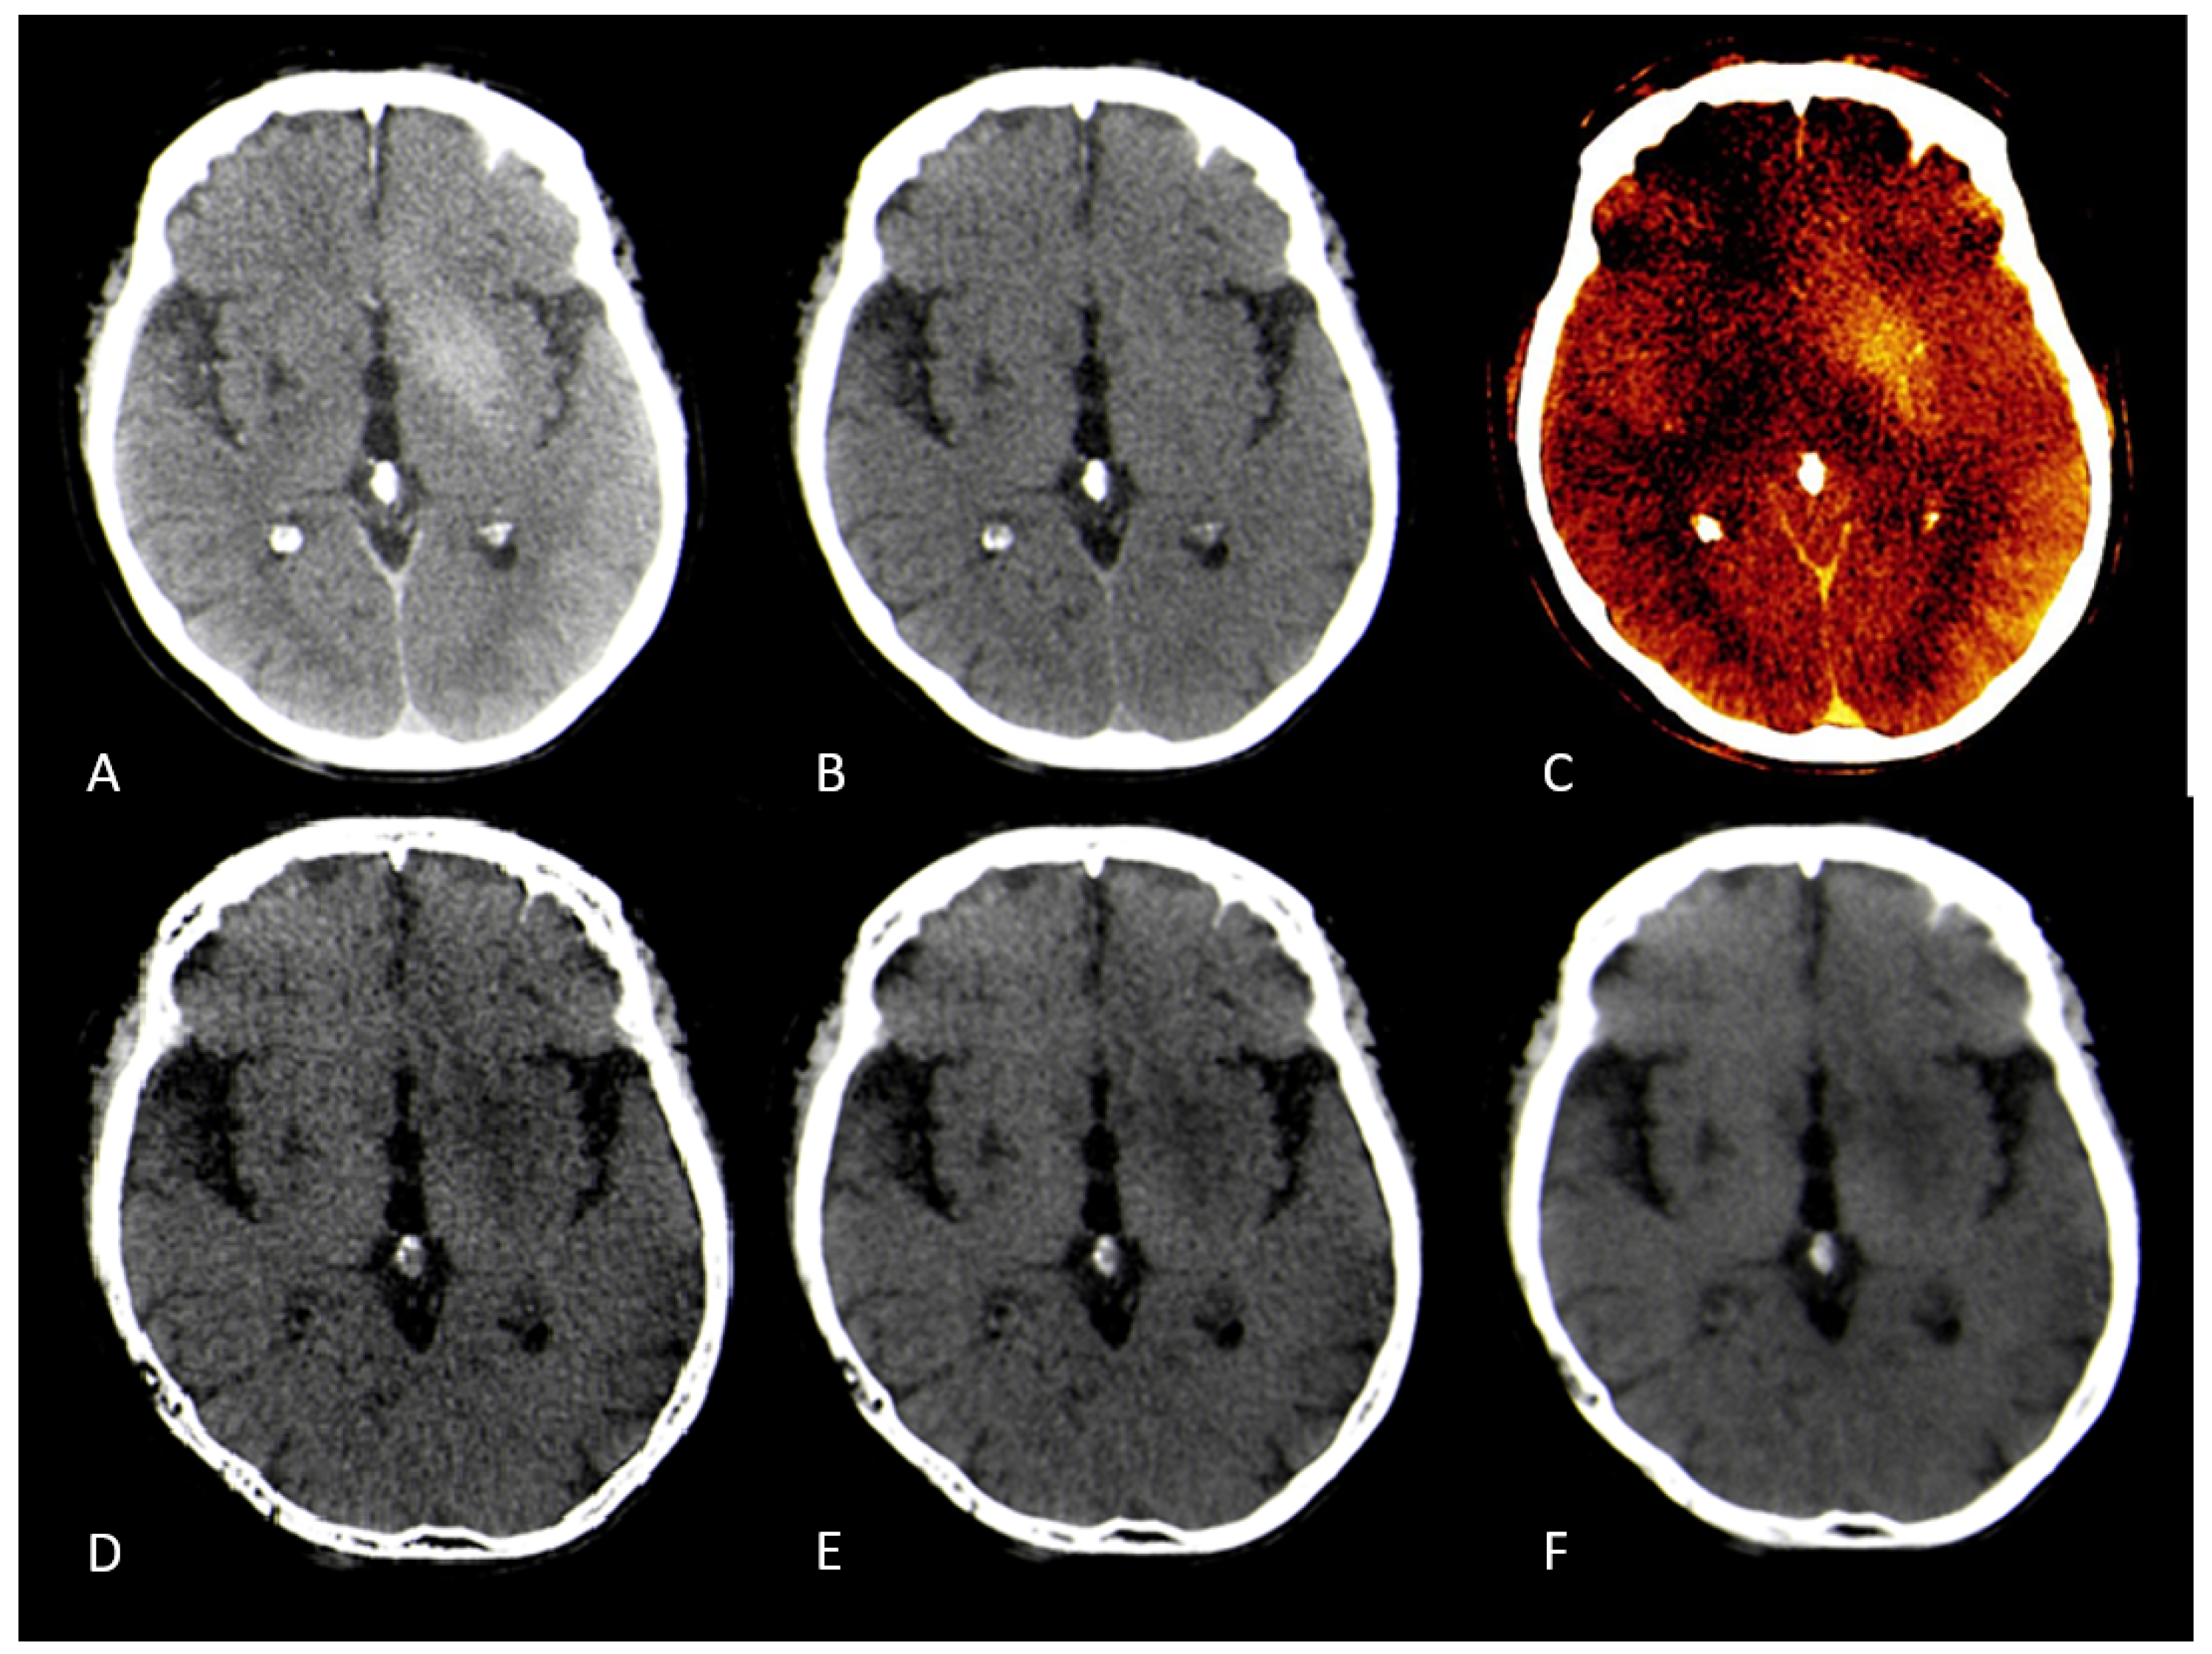

Hounsfield units (HU) were measured by manually placing equally sized regions of interest (ROIs) within the ischemic lesion on the conventional CT image and VNC/edema-maps at different settings of the spatial smoothing filter and iodine ratios. One ROI was placed per patient. Figure 2. Data was tested for normal distribution using the Shapiro-Wilk test. Paired t-tests were applied to normally distributed data, while Wilcoxon signed-rank tests were used for non-normally distributed data. Statistical analyses were performed using Python and R.[19,20]

The median measured Hounsfield Unit (HU) of the infarction area on conventional mixed CT images was 33.73 HU (SD: 4.58), for the default VNC-map 22.96 HU (SD: 3.81), for edema maps at smoothing level 1 (14.39 HU, SD: 4.98), smoothing level 3 (14.50 HU, SD: 3.75), and smoothing level 5 (15.05 HU, SD: 2.65). Figure 2. Normality testing using the Shapiro-Wilk test indicated that median HU values of default VNC and of Edema maps at level 1 of the smoothing filter followed a normal distribution, while all other parameters were non-normally distributed. Significant differences in median Hounsfield unit values were observed between conventional VNC images and edema maps at all levels of smoothing ( p < 0.001 ). Table 2. Figure 3 & Figure 4.

Our results confirm this hypothesis. Edema maps at varying strengths of the smoothing filter show significantly lower Hounsfield Unit (HU) values in infarction tissue compared to conventional VNC images (all p < 0.001 ). Using the device-specific parameter "y" at a smoothing level of 1 resulted in the largest absolute reduction of infarct HU values. In these settings, the image was very noisy compared to mixed CT or the conventional VNC-map. With an increase of the spatial smoothing filter to a setting of 3 there was a marked increase of image quality while maintaining the same infarction detection compared to a smoothing setting of 1 ( p = 0.10 ). Figure 3.

Figure 2. CT-Images of a 71 year old male after recanalization of a M1-occlusion on the left. A: Mixed images with no visible infarction of the basal ganglia, B: Conventional Virtual non-contrast-map with barely visible infarction, C: Follow-up CT after 5 days with Infarction of the basal ganglia, D: Edema-map at smoothing level 1 with visible infarction of the basal ganglia, D: Edema-map at smoothing level 3 with clearly visible infarction of the basal ganglia and good image quality, E: Edema-map at smoothing level 5 with clearly visible infarction of the basal ganglia.